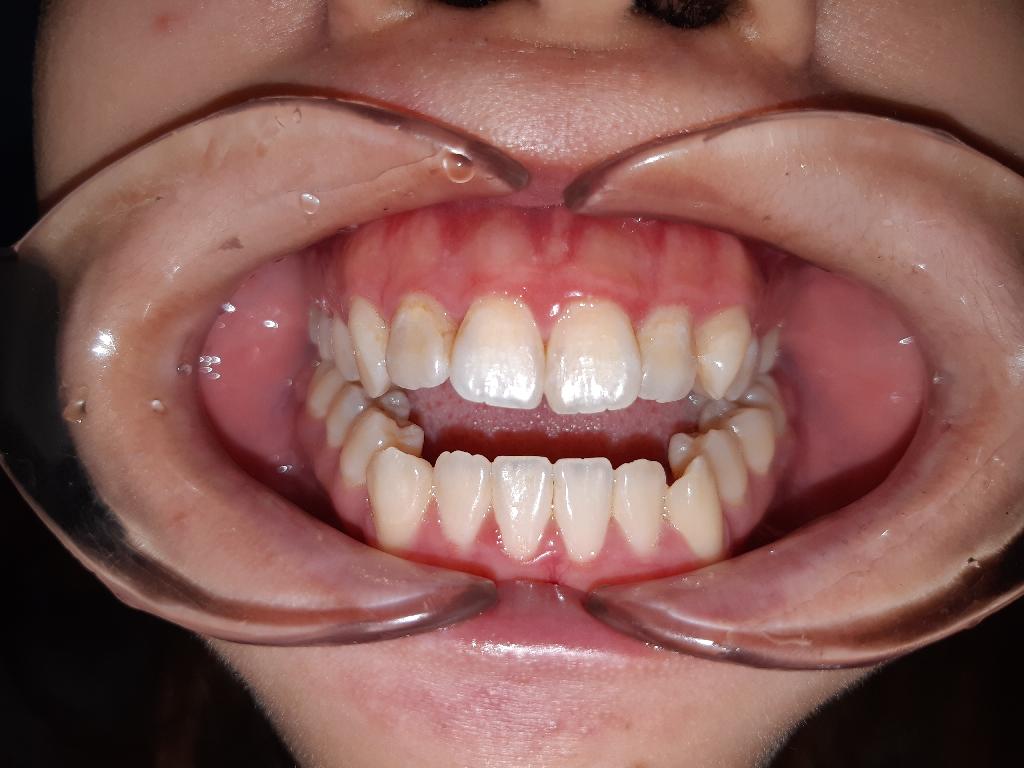

開咬案例 河馬牙醫診所 Dent.Hippo 台中市西屯區重慶路270號 04-23169788 營業時間:早上 9:00~12:00下午13:30~16:30晚上19:00~21:00週一到週六,每周日固定休診 線上預約 河馬牙醫患者好評